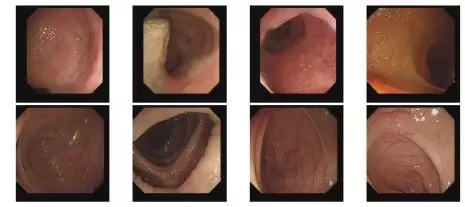

术后随访肿瘤标志物(图5)。术后半年已恢复上班工作,心理及生理健康。2018年3月16日复查PET-CT无复发转移(图6)。2018年3月15日肠镜复查无殊(图7)。2018年3月28日行近段结肠造口纳,术后恢复良好出院,现患者情况稳定。

图7 术后14月复查肠镜无殊